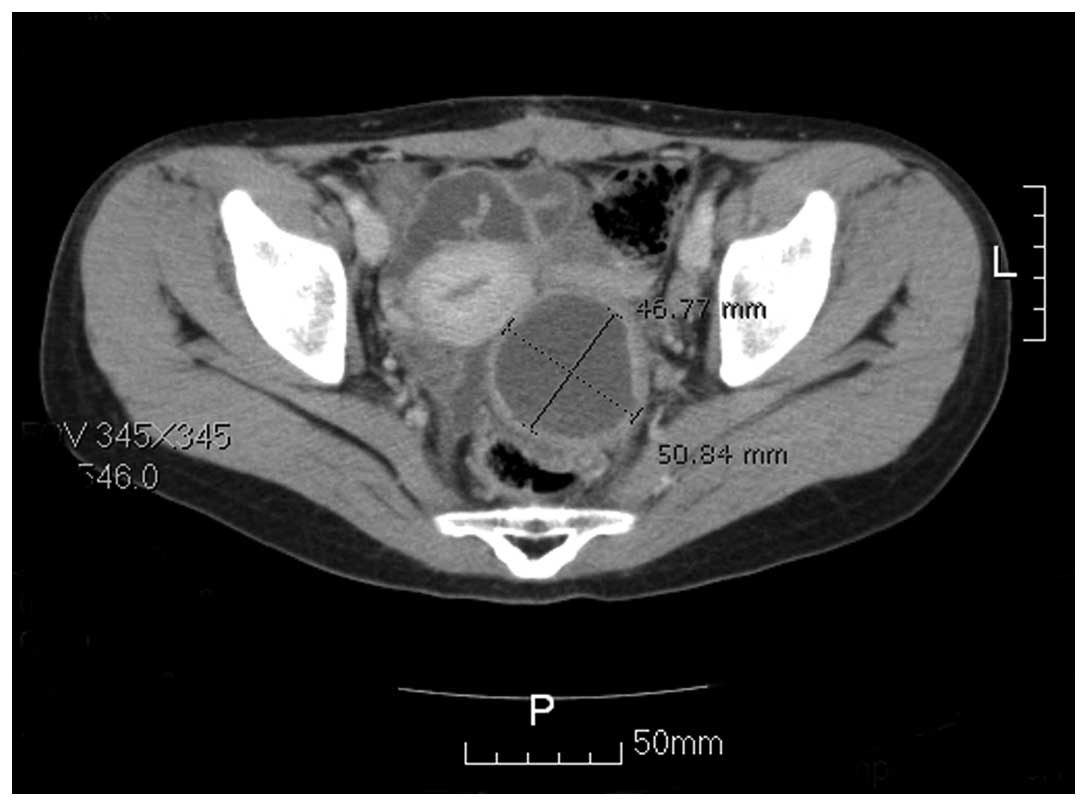

The patient was transferred to the Zheijiang Cancer Hospital (Hangzhou, China) on November 17, 2009. The α-fetoprotein (AFP) serum levels were elevated to 9,859.76 ng/ml (normal level, <10 ng/ml); cancer antigen 125 (CA-125) levels were elevated to 51.90 U/ml (normal level, <35 U/ml); the serum β-human chorionic gonadotropin (β-hCG; normal level, <10 mIU/ml), carcinoembryonic antigen (CEA; normal level, <5.0 ng/ml), carbohydrate antigen 19-9 (CA 19-9; normal level, <37 U/ml) and squamous cell carcinoma (SCC) antigen (normal level, <1.5 ng/ml) were within the normal ranges. A pelvic CT scan revealed a pelvic mass (tumor size, 7.4×9.3 cm; Fig. 1) and an upper abdomen CT showed multiple enlargements of the retroperitoneal lymph nodes.

Figure 1

Computed tomography scan of the pelvic mass (size, 9.4×7.3 cm).

Following two cycles of chemotherapy consisting of bleomycin (15 mg for three consecutive days), etoposide (150 mg for four consecutive days) and cisplatin (40 mg for three consecutive days; termed a BEP regimen), the serum AFP levels decreased to 1,251.27 ng/ml on January 7, 2010 and the CT scan revealed that the tumor size had significantly reduced (Fig. 2). The interval debulking and fertility-sparing surgeries (unilateral left side salpingo-oophorectomy, omentectomy and intumescent lymph node resection) were performed on January 12, 2010. No residual tumor was found and the histopathology report showed a marginal quantity of tumor tissue in the pelvic floor and no positive lymph nodes (Fig. 3). Following surgery, an additional two cycles of chemotherapy, consisting of the aforementioned BEP regimen, were administered continuously. Following surgery and an additional two cycles of the BEP regimen, the serum AFP levels decreased to 8.17 ng/ml following the final administration of the BEP regimen on February 28, 2010.

Figure 2

Computed tomography scan of the tumor. The size of the mass was 4.6×5.0 cm, which was significantly reduced compared with Fig. 1.